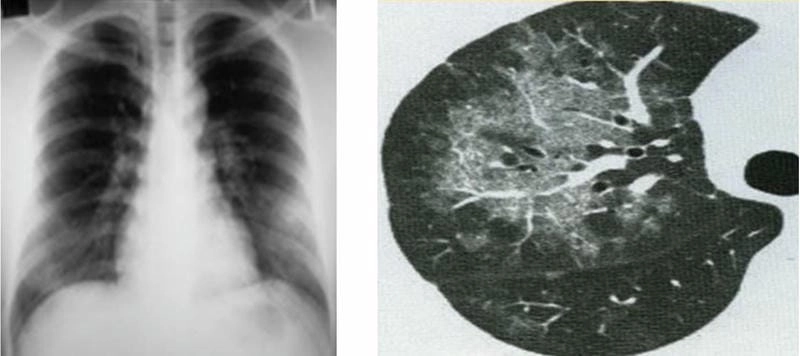

Hình ảnh bệnh lao phổi là tài liệu tham khảo quan trọng giúp người bệnh và bác sĩ dễ dàng nhận biết dấu hiệu bất thường. Việc quan sát hình ảnh X-quang, CT phổi giúp chẩn đoán chính xác mức độ tổn thương và đưa ra phương án điều trị kịp thời.

Bạn sẽ phải rùng mình khi chiêm ngưỡng hình ảnh bệnh lao phổi là như thế nào dưới ống kính y học thực tế. Những bức ảnh chụp X-quang cho thấy phổi bị tổn thương nặng, xuất hiện những đốm trắng mờ như bóng ma ám ảnh. Không chỉ là các tổn thương vật lý, đây còn là những “chứng tích sống” của căn bệnh âm thầm hủy hoại cơ thể qua từng hơi thở. Từ viêm nhẹ đến tổn thương lan rộng, hình ảnh bệnh lao phổi khiến người xem không thể rời mắt vì mức độ nghiêm trọng mà nó thể hiện rõ ràng qua từng chi tiết.

Cảnh báo: tổng hợp ảnh bệnh lao phổi chân thực này không dành cho người yếu tim. Đây là loạt hình ảnh y khoa được các chuyên gia sưu tầm và xác thực, ghi lại quá trình tiến triển của bệnh từ giai đoạn đầu đến giai đoạn nguy kịch. Từng mảng mô phổi bị ăn mòn, xơ hóa, hoại tử được phơi bày rõ nét dưới ánh sáng X-quang lạnh lùng. Những hình ảnh này không chỉ mang tính chất minh họa y học, mà còn là hồi chuông cảnh tỉnh cho bất kỳ ai còn lơ là với căn bệnh nguy hiểm này.